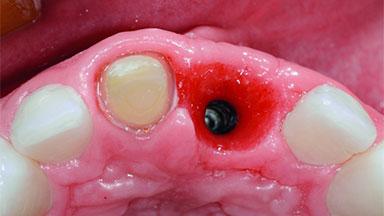

Replacement of an Ankylosed Upper Left Central Incisor: Bone Augmentation and Socket Grafting, Late Placement of an RC Bone Level Implant

Bone Augmentation Horizontal|Simultaneous|Staged

Augmentation Materials Autogenous chips|Xenogenous

Bone Volume Deficient horizontally, requiring prior grafting